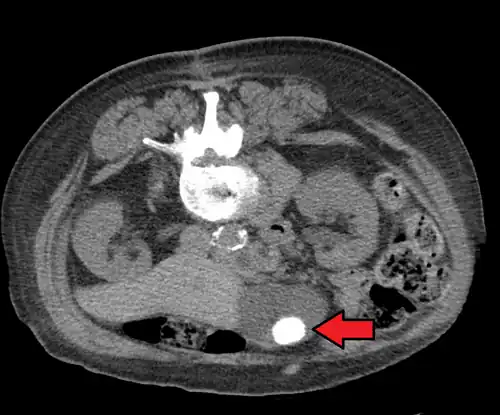

Choledocholithiasis

Choledocholithiasis refers to a gallstone obstructing the common bile duct.[20] Patients typically experience right upper quadrant pain, back pain, jaundice (or yellowing of the skin), decreased appetite, nausea, vomiting, and fever.[13][20] However, choledocholithiasis, just like gallstones, can also be asymptomatic.[14][21] If the patient has symptoms, the physical exam is similar to that of acute cholecystitis.[20] Laboratory studies show an increase in direct (conjugated) bilirubin, gamma-glutamyl transpeptidase (GGT), and alkaline phosphatase. AST and ALT can be elevated or normal.[14][15][21]

Diagnosis is typically confirmed by abdominal ultrasound. Other imaging techniques used are ERCP and MRCP. Gallstone complications may be detected on blood tests.[2]